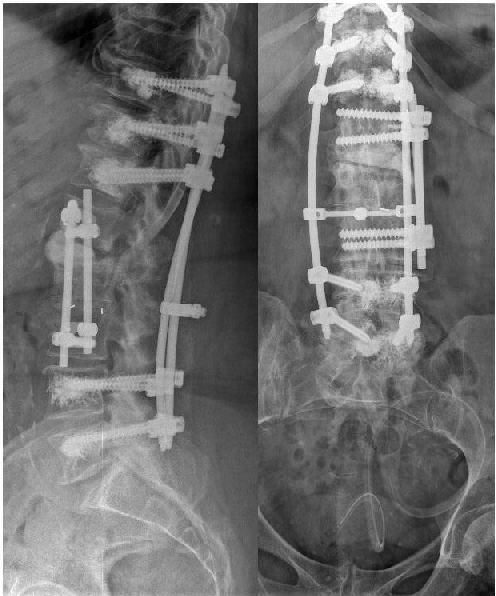

Figure 11. Left: Complete implant removal, radically surgical debridement and external spine fixation with vacuum wound closure (Hoffmann II external fixator, 5.0 mm Pins). Right: X-ray Image of the thoracolumbar spine. External posterior stabilization.

Figure 14: X-ray image of the final internal posterior stabilization (Longitude, Medtronic; cement-augmented pedicle screws, 7.5 mm)